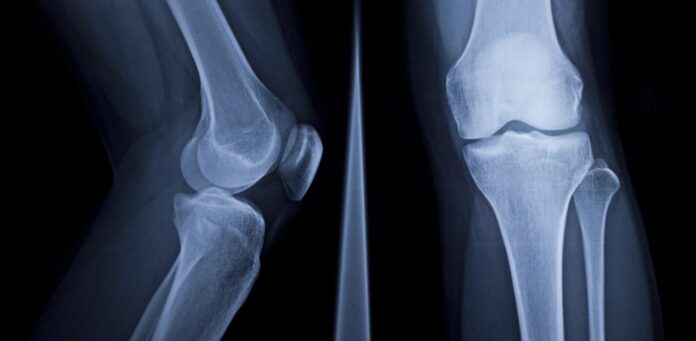

A 2025 scoping review in BJR Open highlights the transformative role of artificial intelligence (AI) in musculoskeletal (MSK) radiology, led by Dr. Mickael Tordjman from Icahn School of Medicine. The review outlines AI applications across seven key areas: accelerated image acquisition, enhanced interpretation, large language models (LLMs), workflow integration, cost-effectiveness, liability concerns, and education. With early emphasis on fracture detection, AI has expanded to include deep learning-based reconstruction and automated classification of bone lesions, improving diagnostic accuracy and efficiency. Notably, AI applications can reduce scan times by up to 53% while maintaining image quality. LLMs streamline report generation, supporting communication among radiologists, clinicians, and patients. Successful AI adoption depends on seamless integration into existing systems, regulatory compliance, and proof of cost-effectiveness. Ultimately, AI serves best as an assistive tool, enhancing radiologist capabilities rather than replacing them. Clear guidelines are essential for safe, responsible implementation.